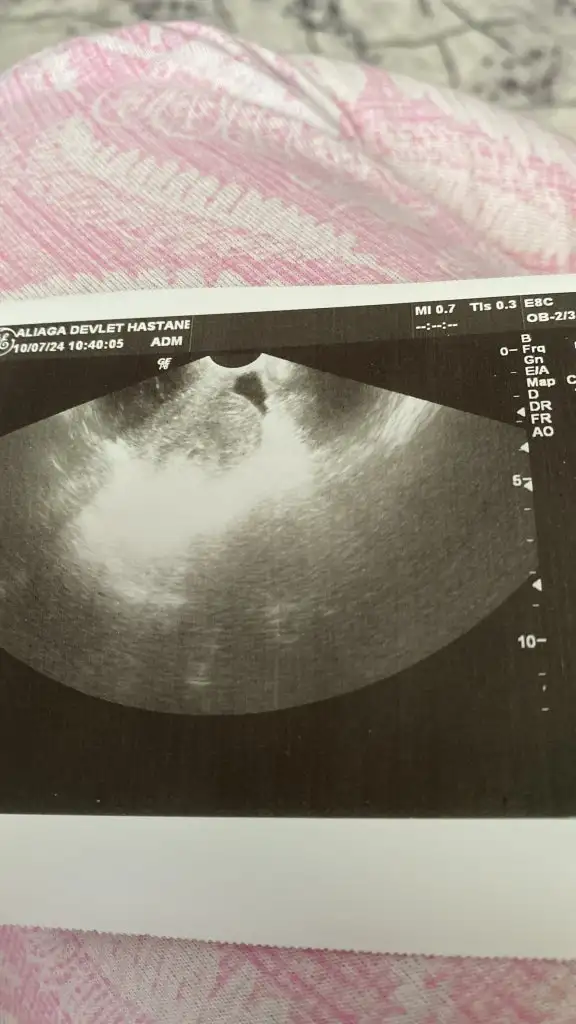

Kızlar endometrial kalınlık 17mm ıntrauterin kavıte 6mm gs beta değerim 1903 4 haftalık hamilelik dedi ama yazılan ulturasyon beni tedirgin etti bu değerleri anlayan var mı sizce süreç nasıl alttan baktı nokta şeklinde elime resimini verdi en üste nokta şeklinde olan yer

• 952F7DD6-24E4-4DF0-9E69-76D2ACFCA5BF.webp